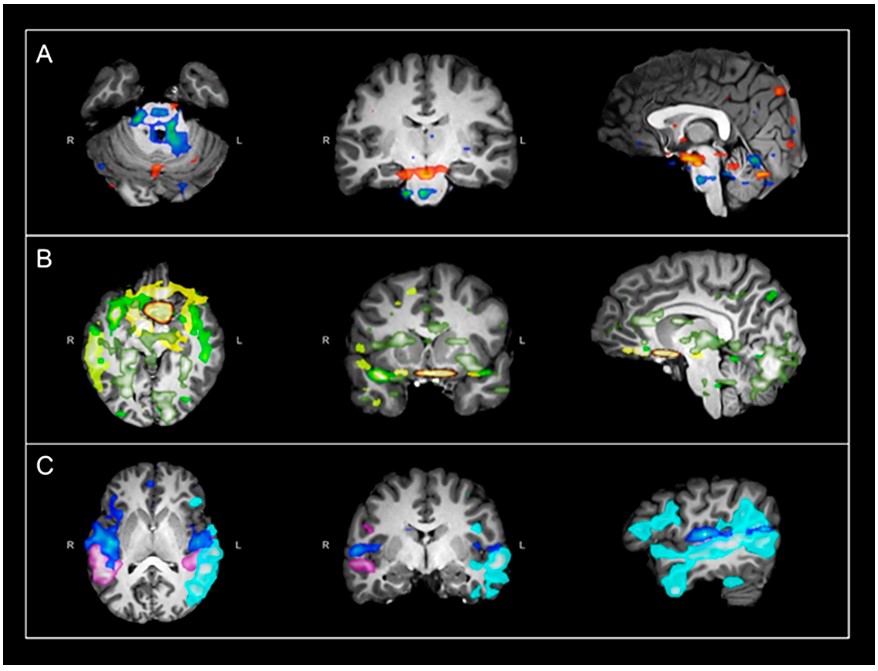

The role of glial cells in schizophrenic brain

Schizophrenia, as a complex neurological disorder, has many distressing symptoms such as hallucinations and some of the common mood or cognitive disorders commonly associated with mental illness. Once suffering from schizophrenia, people’s work and life will be greatly troubled. It is also often associated with other psychiatric disorders, which makes it extremely difficult to treat clinically. However, a diverse of different studies have been able to identify a clear link with neurotransmitter signaling pathways and some brain activity, such as dopamine projection pathways and a significant reduction in gray matter in patients. This research will focus on another dimension, namely the reduction of gray matter volume, to investigate the relationship between oligodendrocyte and astrocyte function and schizophrenia, in an attempt to provide a new vision for the clinical treatment system. In addition, it is expected that this research can also provide a new idea for the development of new drugs for schizophrenia.